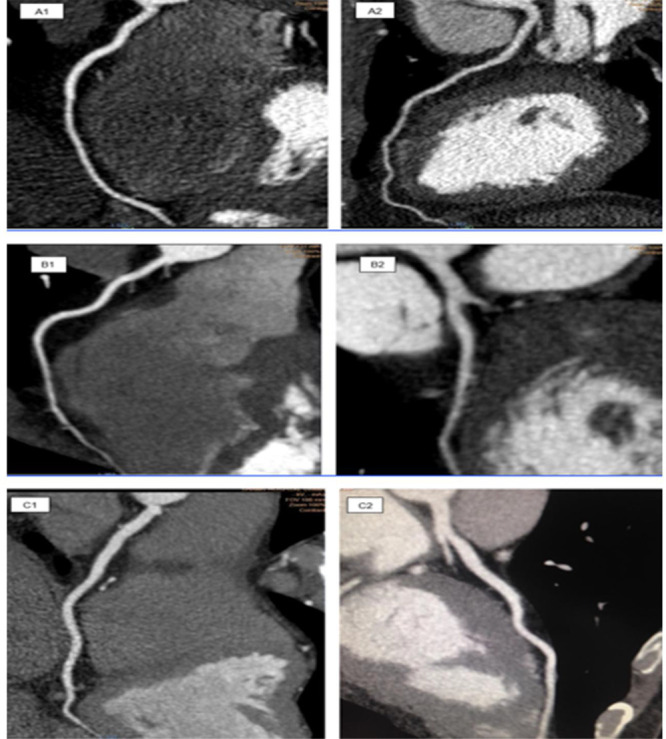

Material and methods: In this cross-sectional study, 66 patients into three main groups: 80 kVp (Group A), 100 kVp (Group B), and 120 kVp (Group C), underwent CCTA. Each group was then divided into two subgroups of BMI<25 and >25 kg/m2. Image noise, mean vascular attenuation at the aorta, signal-to-noise ratio (SNR), and Contrast-to-Noise Ratio (CNR) at five regions of coronary arteries, in which Coronary artery anomalies are common were qualitatively evaluated by subjective image quality analysis.

Results: At each kVp, there were no significant differences in CNR, SNR, noise level, and the effective dose between BMI>25 kg/m2 and BMI<25 kg/m2. The effective radiation dose of groups A, B, and C were 4.16, 8.46, and 14.3 mSv, respectively. Subjective image quality assessment scores were 3.18, 3.5, and 3.73 out of 4 in groups A, B, and C, respectively.

Conclusion: Patient radiation dose using retrospective ECG-gated CCTA can be reduced by about 70% at 80 kVp, which is almost close to the prospective CCTA dose ranges. The retrospective CCTA at 80 kVp can be optimized even in overweight patients (BMI>25 kg/m2).